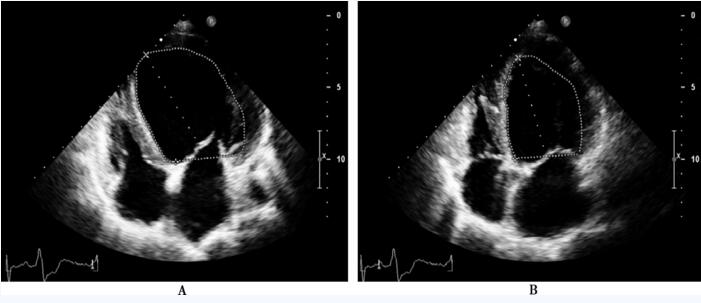

图65-2 小剂量多巴酚丁胺负荷超声心动图[多巴酚丁胺剂量为20μg/(kg•min)]

A:左心室舒张末期;B:左心室收缩末期,Simpson法测量左心室射血分数44%